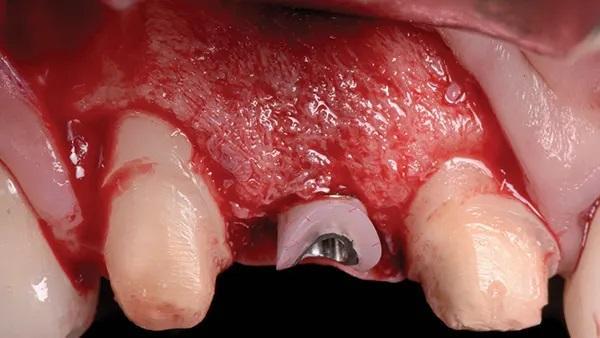

Женщина, 45 лет, с неотягощенным анамнезом, обратилась по поводу замены правого латерального резца верхней челюсти. После освобождения лоскута был выявлен сильный дефицит горизонтального гребня с остаточной шириной кости от 3 мм до 4 мм, что подтверждает данные КЛКТ (Фото 12 и Фото 13).

Фото 12: (Случай 2) Полнослойный разрез с освобождением лоскута в области угла мезиальной линии верхнечелюстного правого бокового резца и премоляра, обнажающий область клыка; обратите внимание на сильный дефицит горизонтального гребня.